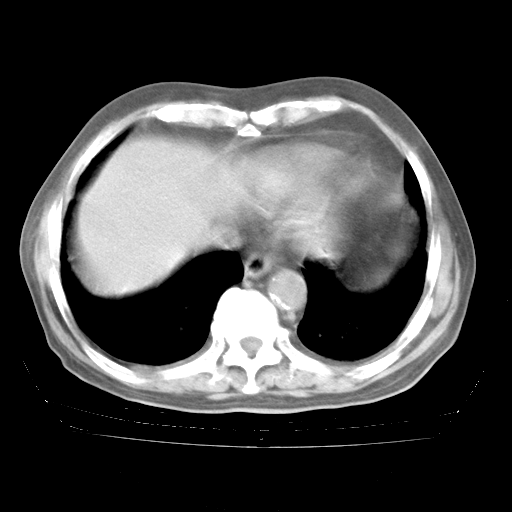

今天部分检查

轻微咳嗽,无痰,(体温正常时)R20次/分,P75次/分,双肺底、腋下可闻及少量捻发音。下肢轻度浮肿。

腹部B超:胆囊壁增厚,肝、胆、胰、脾、肾无异常,肠系膜淋巴结、腹膜后淋巴结无增大。